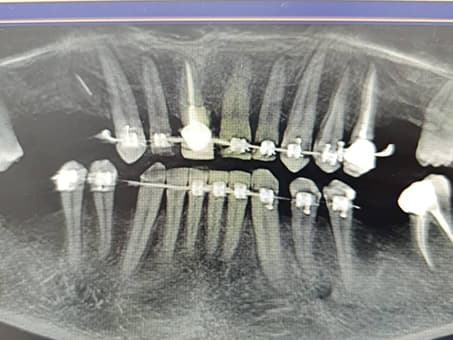

Плановая имплантация при болезни Бехтерева